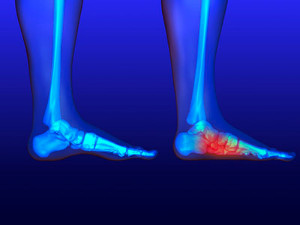

Facts About Flat Feet

Flat feet, or pes planus, come in two main types, which are flexible and rigid. Flexible flat feet show arches that flatten when standing but are visible when sitting, while rigid flat feet have no arch even when sitting. Symptoms often include foot pain, swelling, and difficulty walking or standing for long periods. Risk factors include genetic predisposition, obesity, and certain medical conditions like arthritis. To alleviate discomfort, specific stretches can be helpful. Stretching the Achilles tendon and calf muscles can relieve tension and improve foot flexibility. Foot exercises, such as toe curls and arch lifts, strengthen the muscles supporting the arch. If you have flat feet, it is strongly suggested that you are under the care of a podiatrist who can offer effective relief solutions.

Flatfoot is a condition in which the arch of the foot is depressed and the sole of the foot is almost completely in contact with the ground. About 20-30% of the population generally has flat feet because their arches never formed during growth.

Having flat feet makes it difficult to run or walk because of the stress placed on the ankles.

Alignment – The general alignment of your legs can be disrupted, because the ankles move inward which can cause major discomfort.

Knees – If you have complications with your knees, flat feet can be a contributor to arthritis in that area.